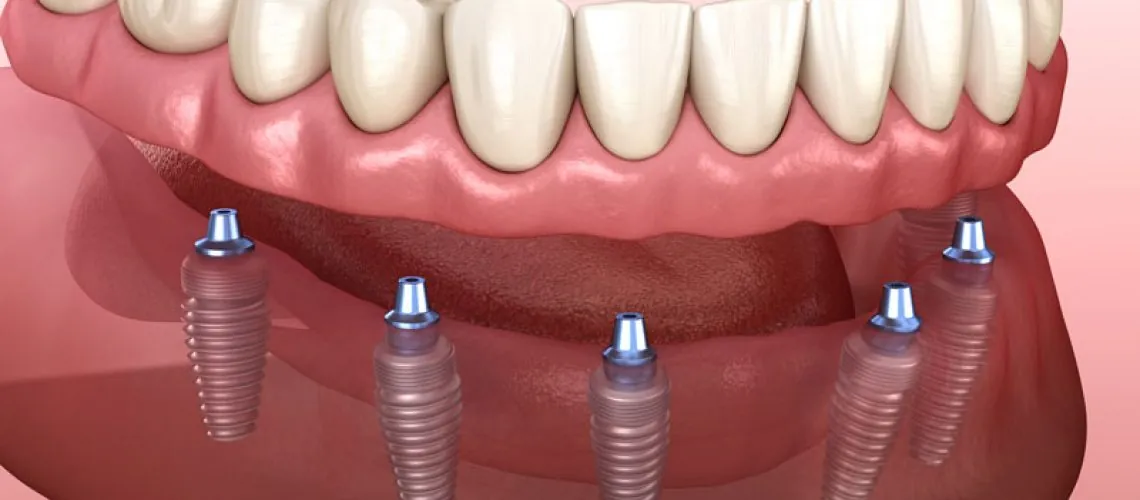

Advances In Dental Implantology